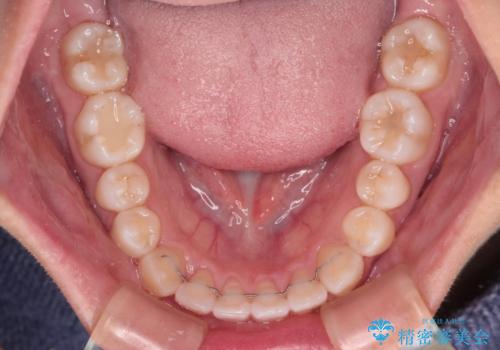

前歯のデコボコを楽して改善 ワイヤー装置による矯正治療

- 前歯のデコボコを治したいとのことで来院された患者様です。

- 矯正治療後の保定が不十分だと後戻り(元の位置に戻ろうとする動き)をします